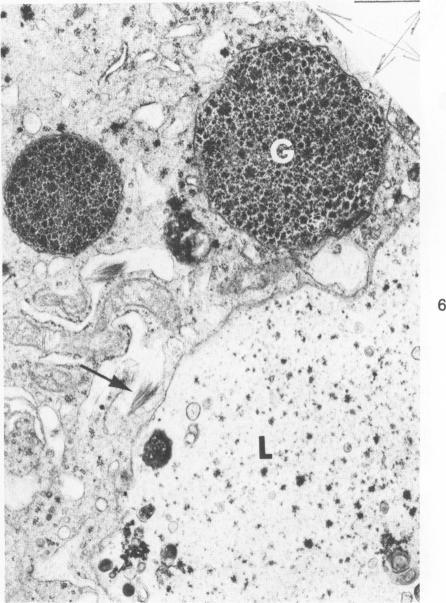

A naturally occurring cardiomyopathy (round heart disease) which is potentiated by inbreeding and a cardiomyopathy produced by furazolidone, a nitrofuran derivative, were studied for an associated alpha1-antitrypsin deficiency in two flocks of turkeys (one inbred for round heart disease and a commercial flock). At 4 weeks of age, the furazolidone-fed birds of both flocks demonstrated a marked increase in mortality and cardiac dilatation associated with disordered hepatic metabolism when compared with controls. Although PAS-positive, diastase-resistant globules were observed in the livers of both strains of turkeys fed furazolidone, these globules were present in lysosomes and not in the rough endoplasmic reticulum as in alpha1-antitrypsin deficiency. The control inbred birds with round heart disease did not demonstrate histologic or biochemical evidence of an alpha1-antitrypsin deficiency. It is proposed that furazolidone in the turkey produces primary hepatic damage that is reflected in lowered total serum proteins, including trypsin inhibitory capacity, and that the alterations produced by furazolidone are superimposed on round heart disease in the inbred flock.

对两群火鸡(一群为患有圆心病的近亲繁殖火鸡,另一群为商业养殖火鸡)进行研究,观察一种由近亲繁殖加剧的自然发生的心肌病(圆心病)以及由硝基呋喃衍生物呋喃唑酮引起的心肌病是否伴有α1-抗胰蛋白酶缺乏症。在4周龄时,与对照组相比,两群中喂食呋喃唑酮的火鸡死亡率显著增加,且出现心脏扩张,并伴有肝脏代谢紊乱。尽管在喂食呋喃唑酮的两株火鸡肝脏中均观察到PAS阳性、抗淀粉酶的小球,但这些小球存在于溶酶体中,而非像α1-抗胰蛋白酶缺乏症那样存在于粗面内质网中。患有圆心病的对照近亲繁殖火鸡未表现出α1-抗胰蛋白酶缺乏症的组织学或生化证据。研究表明,火鸡体内的呋喃唑酮会造成原发性肝脏损伤,这表现为血清总蛋白降低,包括胰蛋白酶抑制能力降低,并且呋喃唑酮所产生的变化叠加在近亲繁殖群体的圆心病之上。